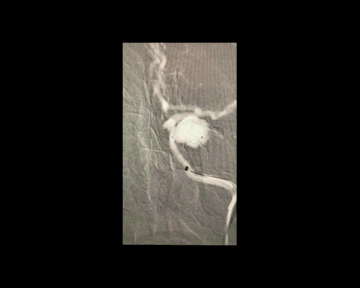

猪尾塑形

猪尾左行和右行

微导管尾端向下直立,头端向前弯曲时,头端相对左偏为左行,右偏为右行。

指向下方的颈内动脉眼段或床突段动脉瘤(颈动脉窝动脉瘤)

指向下方的颈内动脉后交通段或脉络膜段动脉瘤

(1)左侧颈内动脉-猪尾左行

(2)右侧颈内动脉-猪尾右行

病例一